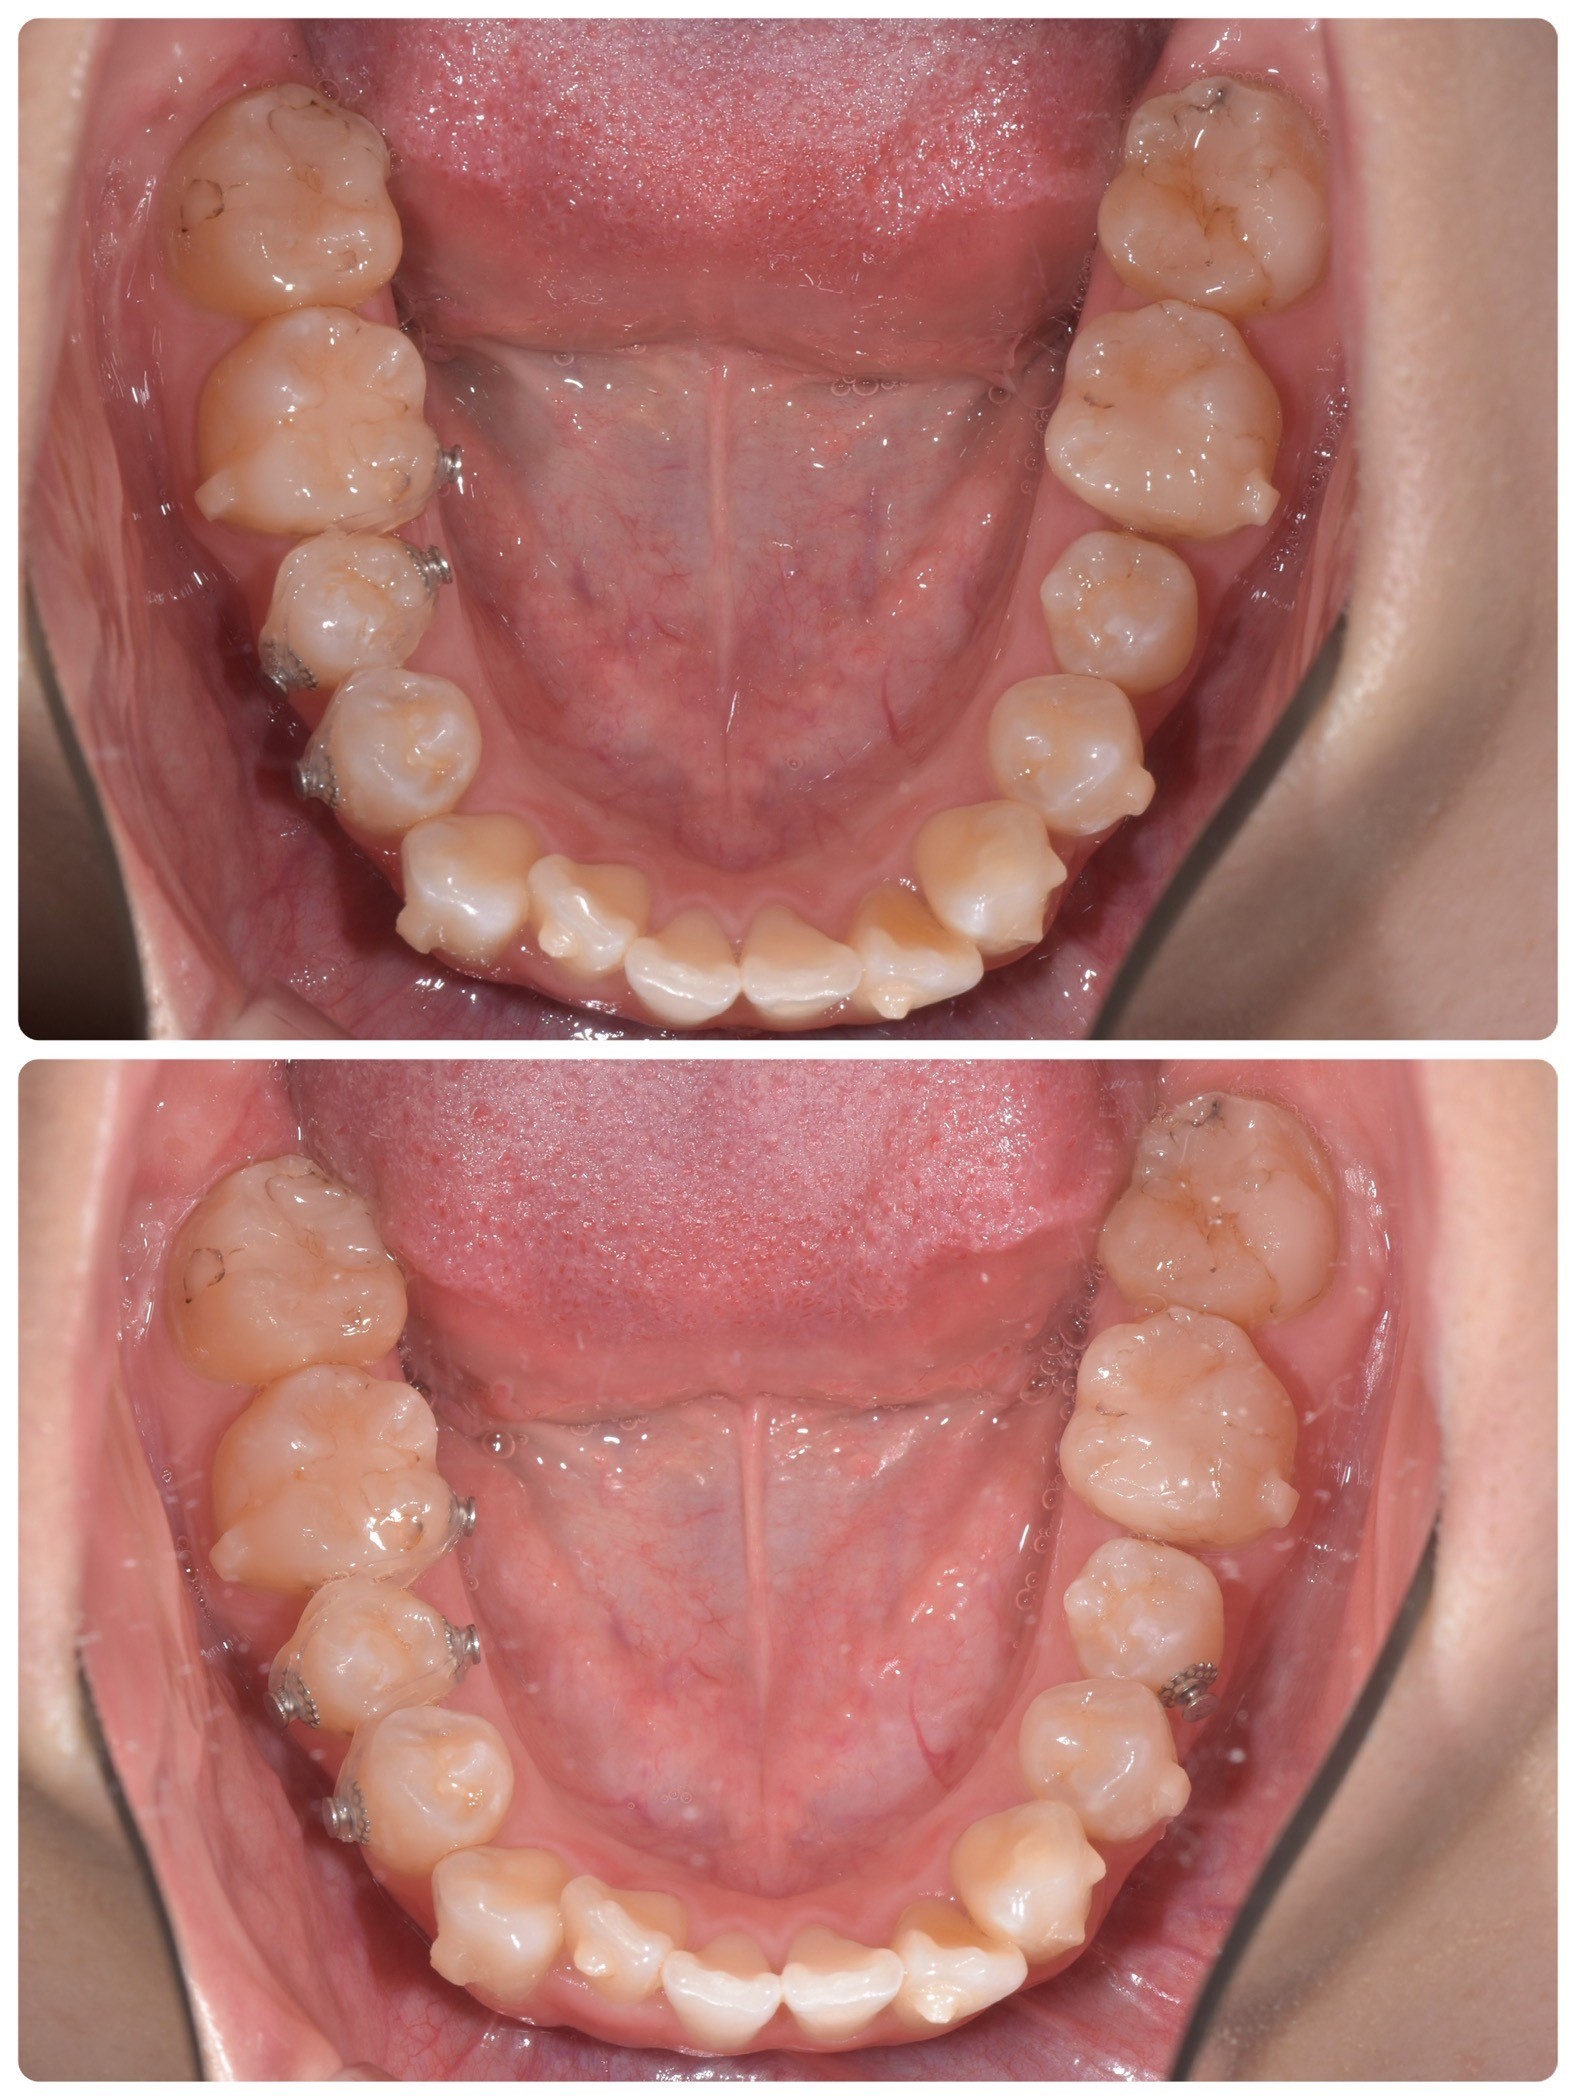

私は下の歯の奥から3番目の歯が、少し回転したように両方生えています。

これを歯の捻転といい、ねじれた様に生えているのでそのように

名前がついています。

そのためこの写真の様に「ボタン」と呼ばれる金属の丸い器具をつけて、

そこにゴムを引っ掛けて歯の動きを促す治療をして頂きました。

上の写真はゴムをかける前、

下の写真はその後1週間の写真です。